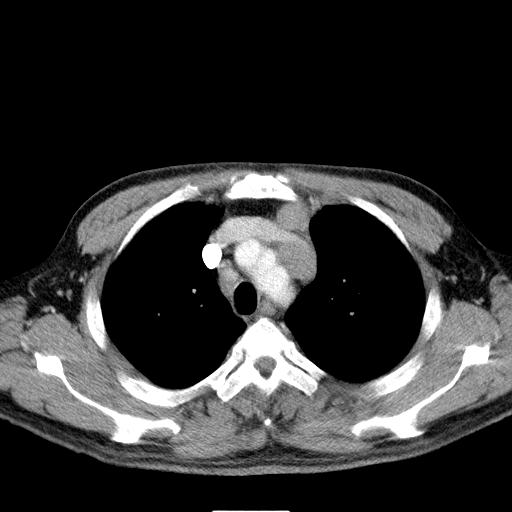

先行ct平扫,纵膈内多发软组织影,ct值约为36hu,以下为增强扫描和腹部平扫。

大家看看肝脏右叶片状低密度影是什么改变啊?

淋巴瘤?肝脏请增强后说啊

多发肿大淋巴结影,肝内改变需结合强化观察